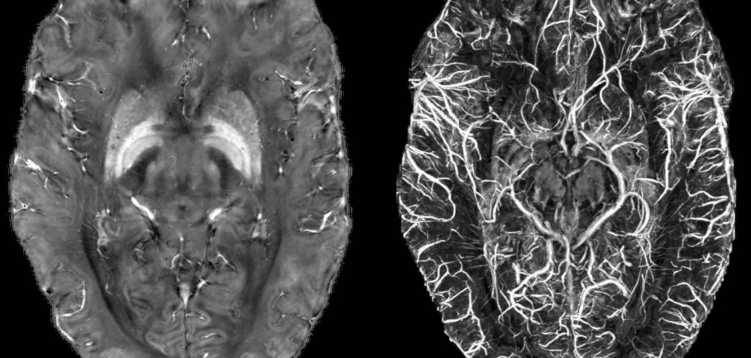

**MRA**는 MRI 기술을 이용하지만 목적이 완전히 다릅니다.

👉 핵심 차이

MRI = 구조 / MRA = 혈관✔ 왜 따로 검사할까?

👉 피 흐름 자체가 문제입니다.그래서 혈관만 따로 강조해서 봅니다.

✔ 대표 검사 목적

- 뇌동맥류 발견

- 혈관 협착 (막힘)

- 뇌졸중 위험 확인

✔ 특징

- 혈관만 3D처럼 확인 가능

- 조영제 없이도 가능한 경우 있음

- MRI보다 목적이 더 명확함